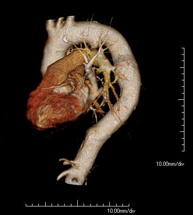

- Angio-TC Cardíaco o TC Cardíaco El angio-TC Cardíaco o Coronariografía no invasiva es una prueba diagnóstica que consiste en el estudio de las arterias del corazón o arterias coronarias mediante el empleo de un equipo de TC Multidetector de última generación y de un contraste yodado, obteniendo imágenes bi y tridimensionales. El TC Multidetector o TCMD permite una adquisición de imágenes tan rápida, que se pueden valorar las arterias coronarias con una alta precisión anatómica: estrechamientos o estenosis, calcificaciones, variantes anatómicas, etc., ya que gracias a su rapidez evita el artefacto que provoca el movimiento constante del corazón (tarda menos de diez segundos en adquirir unas 1000 imágenes). La información obtenida precisa de un tratamiento en estaciones de trabajo con programas especializados en la reconstrucción de las arterias coronarias que permiten valorar el número, la localización y las características de las lesiones. Toda esta información se obtiene de manera no invasiva: solo se requiere la punción de una vena periférica (en el brazo). Es necesario que la frecuencia cardíaca no supere los 75 latidos por minuto, por lo que algunos pacientes deberán realizar un tratamiento previo con un fármaco betabloqueante. El angio-TC Cardíaco o Coronariografía no invasiva es una prueba diagnóstica que consiste en el estudio de las arterias del corazón o arterias coronarias mediante el empleo de un equipo de TC Multidetector de última generación y de un contraste yodado, obteniendo imágenes bi y tridimensionales. El TC Multidetector o TCMD permite una adquisición de imágenes tan rápida, que se pueden valorar las arterias coronarias con una alta precisión anatómica: estrechamientos o estenosis, calcificaciones, variantes anatómicas, etc., ya que gracias a su rapidez evita el artefacto que provoca el movimiento constante del corazón (tarda menos de diez segundos en adquirir unas 1000 imágenes). La información obtenida precisa de un tratamiento en estaciones de trabajo con programas especializados en la reconstrucción de las arterias coronarias que permiten valorar el número, la localización y las características de las lesiones. Toda esta información se obtiene de manera no invasiva: solo se requiere la punción de una vena periférica (en el brazo). Es necesario que la frecuencia cardíaca no supere los 75 latidos por minuto, por lo que algunos pacientes deberán realizar un tratamiento previo con un fármaco betabloqueante.